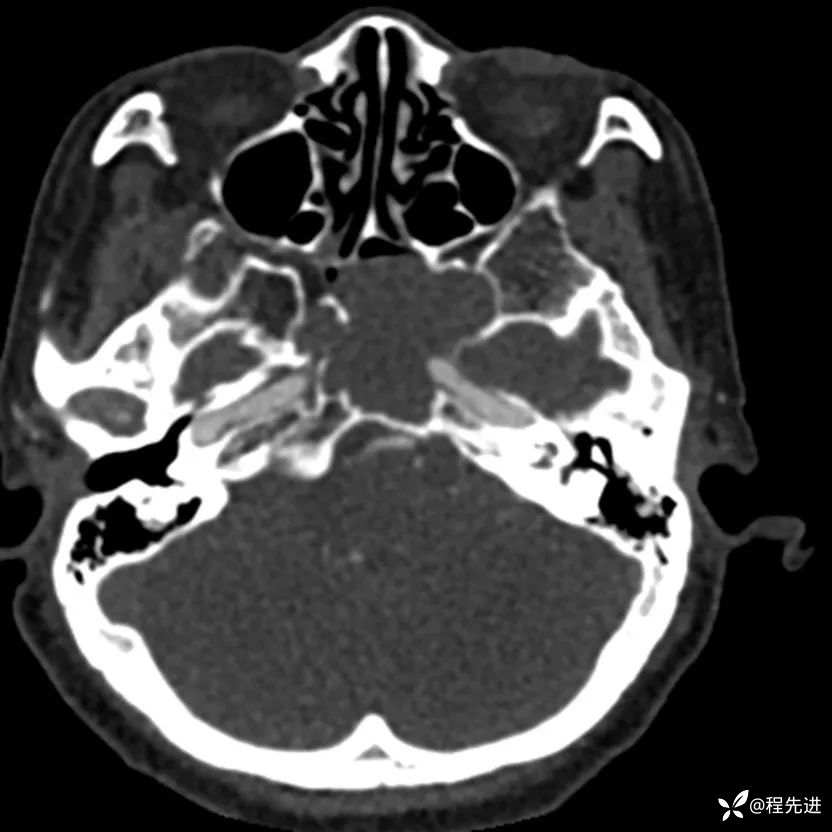

简要病史:外伤检查发现颅底占位

CT增强: